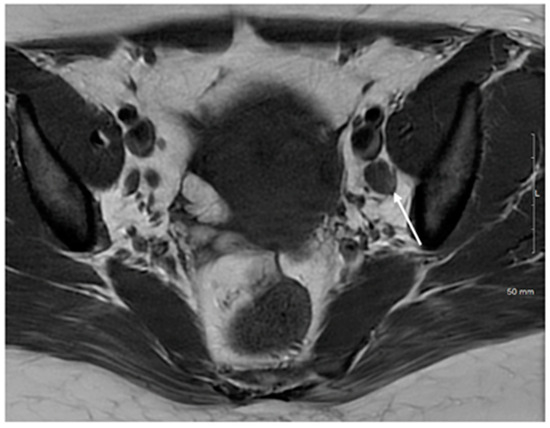

| IIIC | Involvement of pelvic and/or paraaortic lymph nodes |

| IIIC1 | Pelvic lymph node metastasis only |